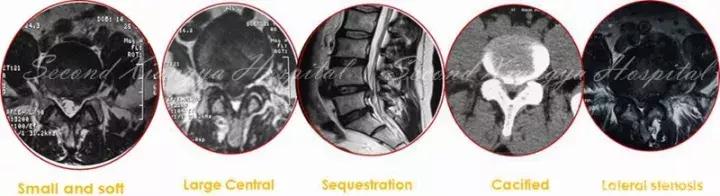

随着经皮内镜技术的进步,其适应症已由单纯的软性突出拓展到处理骨性椎管狭窄和复杂退行性疾患,即由“欺软怕硬”,到“软硬兼吃”。内镜技术已经涵盖了腰椎、颈椎和胸椎退行疾患范畴。然而,由于存在陡峭的学习曲线,为规避风险,增加疗效,树立信心,初期开展应循序渐进,忌超技术能力的盲目应用。

总体来讲,在L5/S1节段,除椎间孔髓核突出外,多数病例建议采用椎板间入路,操作更为容易简捷。对于L4/5以上节段的退行性病变,椎板间入路适合髓核游离、腋下型、较大钙化偏中央、中央或侧隐窝骨性狭窄,以及神经背侧受压为主的病例,对于椎间孔区域的髓核突出(上不超过椎弓下缘,下位于椎弓根中份)、侧隐窝狭窄,神经根腹侧压迫为主的患者,椎间孔入路是较佳选择。如果同时合并椎间孔狭窄或侧隐窝狭窄,可以采用椎板间和椎间孔联合入路。无论采取何种入路,都需要在减少付损伤同时获得充分减压,已到达兼顾微创和治疗的双重目的。

经皮内窥镜在颈椎中的应用,有后路经椎间孔入路,前路经椎间隙和椎体两种入路。后路经椎间孔入路的适用范围主要包括C3-7神经根型颈椎病、颈椎间孔骨性狭窄,亦有部分颈椎管局限性狭窄患者可以采取后路内镜下椎管减压的手术方式。前路经椎间隙适合中央型髓核突出,经椎体用于髓核脱垂类型,不适合颈椎不稳、成角、钙化、间隙高度<4mm和严重压迫者。